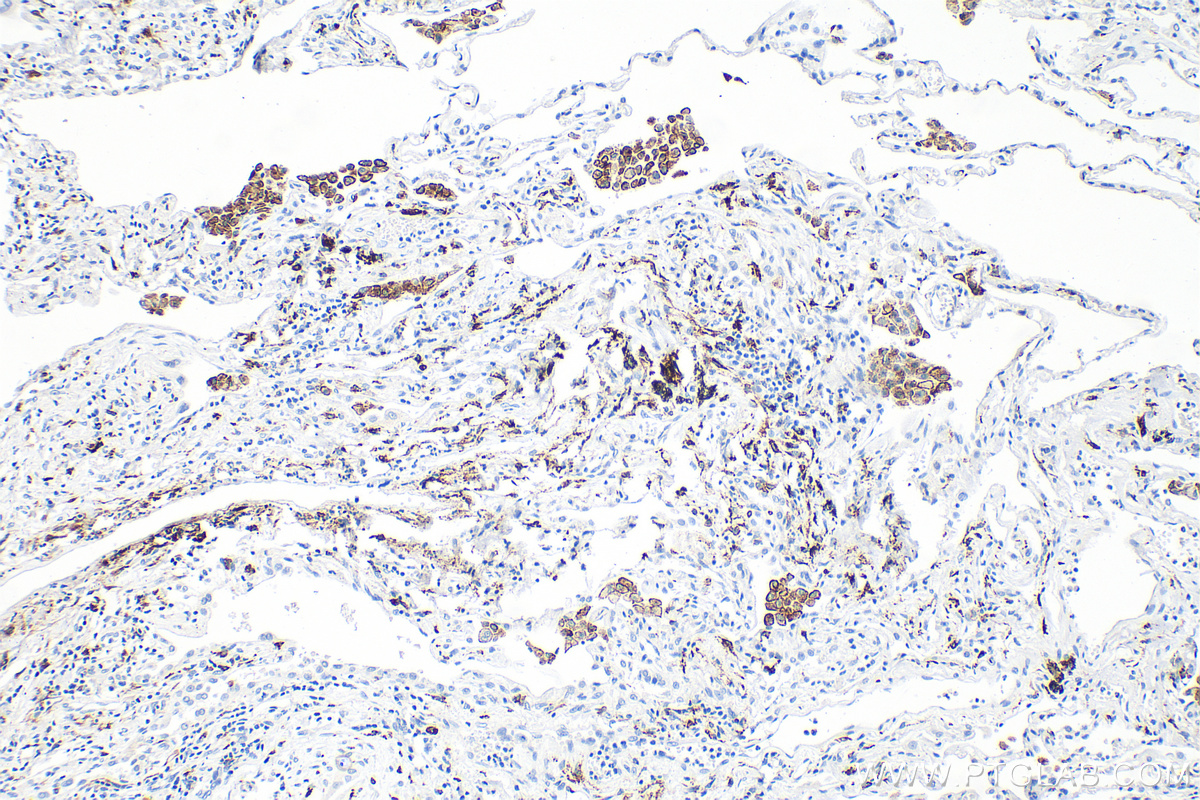

IHC staining of human lung cancer using 81525-1-RR (same clone as 81525-1-PBS)

Immunohistochemical analysis of paraffin-embedded human lung cancer tissue slide using 81525-1-RR (CD206 antibody) at dilution of 1:2000 (under 10x lens). Heat mediated antigen retrieval with Tris-EDTA buffer (pH 9.0). This data was developed using the same antibody clone with 81525-1-PBS in a different storage buffer formulation.